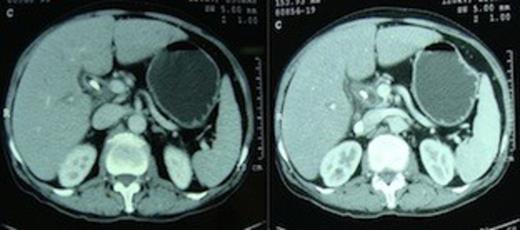

A 55 year non-diabetic male with painless progressive jaundice, pruritus and weight loss of 3 month duration was admitted in emergency with cholangitis. Investigations revealed a total leukocyte count of 17 000/cu.mm, total bilirubin: 222.3 μmol/L, direct: 136.8 μmol/L and alkaline phosphatase level: 1153 U/L. Side viewing endoscopy showed an ulceronodular growth at papilla, a papillotomy and endoscopic biliary plastic stenting was done. Neither cholangiogram nor pancreaticogram was obtained in view of cholangitis. Once his cholangitis resolved, he was referred for surgery. Pre-operative triple phase CT (computed tomography) scan of the abdomen showed a resectable ill-defined hypodense mass in the region of ampulla, the pancreatic head and uncinate were normal however the neck, body and tail of pancreas were absent (figure 1,2).

Computed tomography scan showing pancreatic head and uncinate process with absence of neck anterior to the portal vein. An ill-defined hypodense mass is seen in the ampullary region. Biliary stent is in situ.